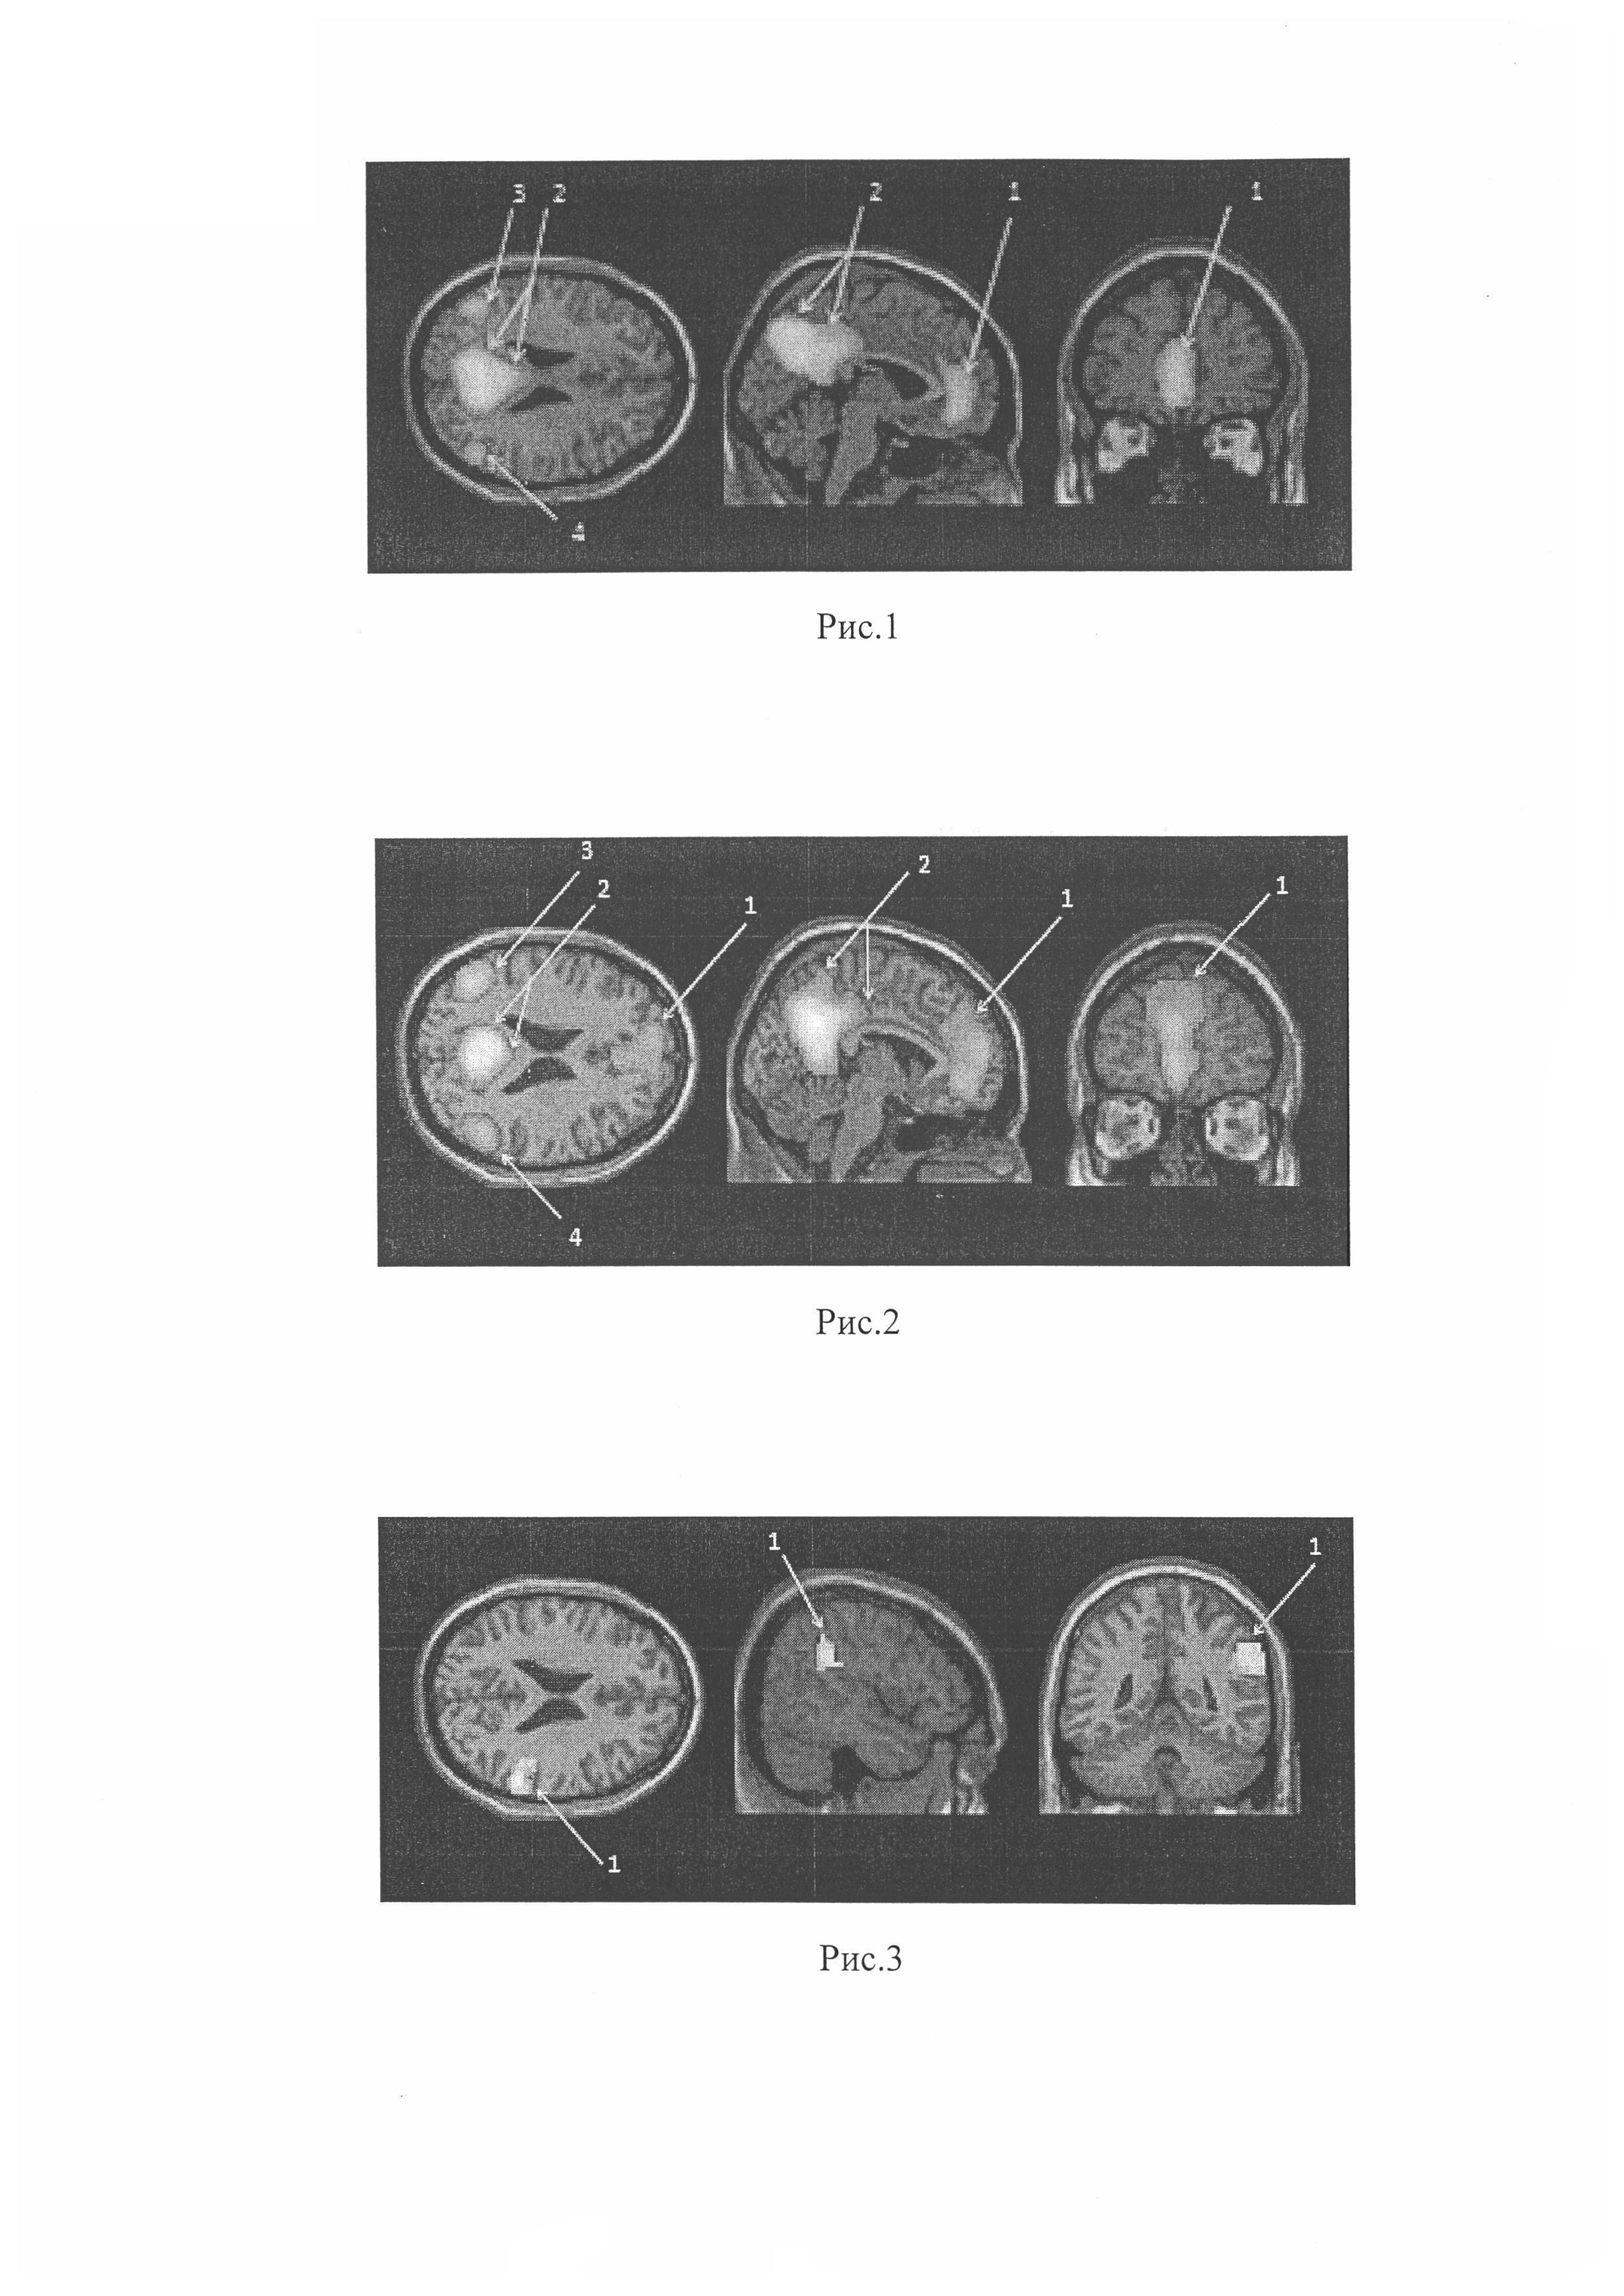

Изобретение относится к области медицины, в частности к неврологии, и может быть использовано для диагностики текущего нейродегенеративного процесса при болезни Паркинсона. Нейродегенеративный процесс при болезни Паркинсона имеет нелинейный характер: основная гибель нейронов происходит за несколько лет до манифестации клинических симптомов или в первые 2-3 года болезни. Это делает чрезвычайно актуальным поиск биомаркеров, которые позволили бы достоверно верифицировать развивающуюся патологию в ее скрытой (латентной) стадии. И только ранняя диагностика является залогом успеха превентивной нейропротективной терапии, подходы к которой интенсивно разрабатываются в ведущих лабораториях мира. Данные многочисленных клинических и экспериментальных исследований показывают, что при большинстве нейродегенеративных заболеваний латентная фаза длится в среднем около 6-8 лет, а затем сравнительно быстро развивается манифестация явных клинических проявлений болезни. Именно эти несколько лет составляют наиболее благоприятное "терапевтическое окно", в течение которого необходимо стремиться диагностировать патологию и предотвратить или хотя бы отсрочить наступление необратимых изменений (Иллариошкин С.Н. Ранняя диагностика нейродегенеративных заболеваний. Журнал "Нервы", 2008, №1, с. 11-13). В этой связи установление биомаркеров ранней и пресимптоматической стадии нейродегенеративного процесса играет важную роль в выявлении неблагополучия со стороны центральной нервной системы. В неврологии наиболее перспективными считаются три группы биомаркеров: - нейрофизиологические и нейропсихологические (изменение нормальной картины биоэлектрической активности мозга при электроэнцефалографии, тонкие изменения психики и профиля личности при использовании специальных тестов и др.); - молекулярно-биохимические (например, повышение в цереброспинальной жидкости и крови пациентов уровня некоторых белков, строго специфичных для вещества мозга); - нейровизуализационные (выявление с помощью специальных методик рентгеновской, магнитно-резонансной или радиоизотопной компьютерной томографии тех или иных функционально-биохимических изменений в веществе мозга, либо тонких признаков нарастающего уменьшения объема отдельных ядер - скоплений нейронов в определенных отделах мозга). (Иллариошкин C.H. Ранняя диагностика нейродегенеративных заболеваний .Журнал "Нервы", 2008, №1, с. 11-13). Однако специфичность и чувствительность большинства применяемых тестов пока недостаточна, а ряд исследовательских технологий (таких как позитронно-эмиссионная томография) в силу их сложности и высокой стоимости остаются практически недоступными для реального применения на практике. Большой интерес в последние годы вызывают новые технологии нейровизуализации, такие, как транскраниальная сонография (выявление гиперэхогенности черной субстанции) или специальные режимы магнитно-резонансной томографии (МРТ)-исследования (морфометрия, трактография и др.). На сегодняшний день известен способ диагностики нейродегенеративного процесса при болезни Паркинсона путем волюметрической морфометрии головного мозга по данным высокопольной магнитно-резонансной томографии. Отсутствие выраженных атрофических изменений вещества головного мозга в группах с начальными и выраженными клиническими проявлениями болезни Паркинсона (БП) по сравнению с больными цереброваскулярным заболеванием (ЦВЗ), где уже имеются статистически значимые отличия как по сравнению с группой контроля, так и с группой с начальными клиническими проявлениями БП, отражают особенности нейродегенеративного процесса при БП и органические изменения при ЦВЗ (Богданов P.P., Мананникова Е.И., Абраменко А.С., Маратканова Т.В., Котов С.В. Морфометрические показатели нейродегенеративного процесса при болезни Паркинсона и хронической ишемии головного мозга. Журнал неврологии и психиатрии, 2013, №10, с. 40-44). Однако данная методика имеет ряд недостатков, в частности некорректную интерпретацию отдельных участков белого вещества полушарий и восприятие ствола мозга как однородной структуры, образованной только белым веществом. Это накладывает ряд ограничений в применении данной методики для оценки состояния дофаминергических структур и требует разработки новых технических и методологических подходов. Техническим результатом заявленного нами способа является повышение точности диагностики нейродегенеративного процесса при болезни Паркинсона на раннем этапе его проявления. Технический результат достигается тем, что диагностику нейродегенеративного процесса при болезни Паркинсона проводят путем исследования головного мозга с помощью функциональной магнитно-резонансной томографии в состоянии покоя (фМРТп), при этом посредством фМРТп выявляют зоны спонтанной нейрональной активности сети пассивного режима работы головного мозга (СПРР), представленные отделами предклинья, задними отделами поясных извилин, медиальными лобными отделами, нижними теменными дольками правого и левого полушарий головного мозга и при наличии снижения спонтанной нейрональной активности только в нижней теменной дольке правого полушария СПРР относительно уровня спонтанной нейрональной активности СПРР группы контроля диагностируют нейродегенеративный процесс при болезни Паркинсона. Способ осуществляется следующим образом. Пациенту проводят нейровизуализационное обследование на магнитно-резонансном томографе Siemens MAGNETOM Avanto с величиной магнитной индукции 1,5 Тесла, которое включает в себя определенный порядок исследования: для исключения грубых патологических изменений в головном мозге исследование проводят в стандартном режиме Т2 взвешенных изображений, затем проводят фМРТп. Функциональная магнитно-резонансная томография покоя в процессе исследовании головного мозга обеспечивает анализ низкочастотных колебаний (менее 0,1 Гц) BOLD-сигнала (blood oxygenation leveldependent contrast - контрастность, зависящая от степени насыщения крови кислородом) в получаемых при обследовании временных последовательностях (Fox MD, Greicius M. Clinical applications of resting state functional connectivity. Front Syst Neurosci 2010; 4: 19), что косвенно позволяет оценить спонтанную нейрональную активность головного мозга в покое. При этом посредством фМРТп выявляют зоны спонтанной нейрональной активности сети пассивного режима работы головного мозга (СПРР), представленные отделами предклинья, задними отделами поясных извилин, медиальными лобными отделами, нижними теменными дольками правого и левого полушарий головного мозга. При проведении фМРТп пациентам предлагают лежать как можно более неподвижно, с закрытыми глазами (с целью исключения стимуляции зрительного анализатора), в наушниках (для уменьшения стимуляции слухового анализатора), стараться не засыпать и не думать ни о чем конкретном. При этом продолжительность исследования составляет 6 минут 20 секунд (регистрировали 36 срезов головного мозга); в результате для каждого обследуемого получают 100 измерений всего объема головного мозга. Для обработки данных фМРТп используют пакет программ SPM и анализируют методом анализа независимых компонент в приложении GIFT на базе MATLAB. Предпроцессинг проводят в программе SPM. При предварительном статистическом анализе данных фМРТп для каждого обследуемого получают данные о зонах спонтанной нейрональной активности в виде цветных карт. Те же данные также представляют в числовом отображении с указанием их объема-кластера в вокселах, уровня статистической значимости зон активности (PFWEcorr), Т-критерия и координат в стереотаксическом пространстве MNI (Montreal Neurological Institute anatomical template). Данный анализ проводят для каждого обследованного субъекта отдельно (порог статистической значимости - p<0,05, FWE corrected). На основании полученных данных была определена СПРР, где выявились зоны спонтанной нейрональной активности с высоким уровнем статистической значимости, где при наличии снижения спонтанной нейрональной активности только в нижней теменной дольке правого полушария СПРР относительно уровня спонтанной нейрональной активности СПРР группы контроля диагностируют нейродегенеративный процесс при болезни Паркинсона. Необходимо отметить, что большинство работ, обследующих сети покоя, направлены на изучение моторных зон коры и изменений функциональной коннективности (ФК) в них. С целью определения зон сети пассивного режима работы головного мозга (СПРР), в которую входят участки серого вещества предклиньев, задних отделов поясных извилин, медиальных лобных отделов, нижних теменных областей, участвующие в когнитивных процессах и зрительно-пространственном восприятии, нами был использован анализ независимых компонент (программа GIFT - Group ICA fMRI Toolbox, - групповой анализ независимых компонент для данных фМРТ). Были обследованы пациенты с впервые выявленной болезнью Паркинсона до начала терапии и для сравнения пациенты с БП, находящиеся на дофаминергической терапии, и группа здоровых добровольцев - 3 независимых группы: 1. Группа здоровых добровольцев. В нее вошли 18 здоровых добровольцев без заболеваний центральной нервной системы, из них 9 женщин, средний возраст (медиана, 1 и 3 квартили) составил 43,0 года [27;71]. 2. Группа пациентов, находящихся на дофаминергической терапии. 16 пациентов с болезнью Паркинсона, из них 10 женщин. Все пациенты находились на лечении агонистами дофаминовых рецепторов и/или препаратами леводопы. Средний возраст пациентов составил 62,5 [50;76] года. Средняя продолжительность заболевания составляла 33 [18;60] месяца или 2 года 9 месяцев. 3. Группа пациентов на ранних стадиях заболевания. В группу вошло 9 пациентов, из них 4 женщины, с впервые выявленной болезнью Паркинсона без фармакологического лечения. Средний возраст составил 56,44 [39;66] года. Средняя продолжительность заболевания составляла 20 [10;36] месяцев. Проведение исследования было одобрено локальным этическим комитетом; пациенты и здоровые добровольцы подписали информированное согласие на проведение обследования. Все исследуемые были правши. Всем пациентам был проведен неврологический осмотр с использованием шкал UPDRS, МоСа, Hoehn-Yahr, батареи лобных тестов, госпитальной шкале тревоги и депрессии (HADS). Исследование проводили на магнитно-резонансном томографе Siemens MAGNETOM Avanto с величиной магнитной индукции 1,5 Тесла, которое включало в себя порядок исследования: последовательность для получения стандартного режима Т2 ВИ - для исключения грубых патологических изменений в головном мозге, данных функциональной МРТп и анатомических данных в режиме MPR. При проведении фМРТп пациентам предлагалось лежать как можно более неподвижно, с закрытыми глазами (с целью исключения стимуляции зрительного анализатора), в наушниках (для уменьшения стимуляции слухового анализатора), стараться не засыпать и не думать ни о чем конкретном. Проведение фМРТп и получение результатов осуществляли, как описано выше. При сравнении трех независимых групп были получены следующие данные. Во всех группах был определен уровень спонтанной нейрональной активности СПРР, представленной отделами предклинья, задними отделами поясных извилин, медиальными лобными отделами, нижними теменными дольками правого и левого полушарий головного мозга, из которых были выбраны зоны активности с высоким уровнем статистической значимости (pFWEcorr<0,05). Зоны СПРР на примере данных группы контроля представлены на рис. 1 «Общий вид СПРР по данным фМРТп головного мозга здорового добровольца»: представлена локализация зон данной сети, где 1 - медиальные отделы лобных долей. 2 - задние отделы поясных извилин и отделы предклинья. 3 - нижние отделы теменных долей левого полушария головного мозга. 4 - нижние отделы теменных долей правого полушария головного мозга. В отличие от здоровых добровольцев и по сравнению с другими зонами у пациентов 2-й группы определилось уменьшение спонтанной нейрональной активности в нижней теменной дольке правого полушария - в зоне, участвующей в зрительно-пространственном восприятии (см. рис. 2). На рис. 2 представлен общий вид СПРР по данным фМРТп головного мозга пациента с БП, находящегося на дофаминергической терапии (а именно снижение интенсивности активации в зоне 4 (нижние отделы теменных долей правого полушария головного мозга) по сравнению с зоной 3 (левое полушарие) и другими зонами (1 и 2). У пациентов 3-й группы в сравнении с группами 1 и 2 также определялось уменьшение спонтанной нейрональной активности в нижней теменной дольке правого полушария СПРР. Причем оно было более выражено по сравнению со 2-й группой, что отражено на рис. 3. На рис. 3 показано сравнение двух групп (2-й и 3-й), где было определено статистически значимое снижение спонтанной нейрональной активности только в нижней теменной дольке правого полушария СПРР, а именно более выраженное снижение интенсивности активации в зоне 4 правого полушария группы 3 по сравнению с той же зоной пациентов 2-й группы). Кроме того, нами было выявлено, что изменение спонтанной нейрональной активности в нижней теменной дольке правого полушария коррелирует с данными по шкале МоСа и UPDRS (МоСа - Монреальская шкала когнитивной оценки разработана для быстрого скрининга мягких когнитивных нарушений; унифицированная шкала UPDRS используется для оценки когнитивных нарушений при длительном течении БП). Чем выше оценка по шкале МоСа, т.е. чем сохраннее когнитивная функция, тем выше спонтанная нейрональная активность в данной зоне. Чем выше оценка по шкале UPDRS, тем более выражено снижение когнитивной функции и тем меньше спонтанная нейрональная активность в данной зоне у всех пациентов с БП (табл. 1). Данные были подтверждены результатами проведенного множественного регрессионного анализа со шкалами МоСа и UPDRS и данной зоной. Наряду с уменьшением спонтанной нейрональной активности в вышеуказанной зоне, у пациентов третьей группы также было выявлено увеличение спонтанной нейрональной активности в других зонах, входящих в состав СПРР - медиальных отделах левой лобной доли, угловых извилинах правого и левого полушарий большого мозга, что отражает явление нейропластичности. Таким образом, полученные с помощью методики фМРТп данные с выявлением сети пассивного режима работы головного мозга у нелеченых больных БП говорят о снижении спонтанной нейрональной активности в нижней теменной дольке правого полушария и входящей в ее состав надкраевой извилине, участвующей в когнитивных процессах, и могут рассматриваться как биомаркеры текущего нейродегенеративного процесса у пациентов с БП, не принимавших терапию. Выявление снижения спонтанной нейрональной активности в нижней теменной дольке доказывает наличие нейродегенеративного процесса при болезни Паркинсона, что крайне важно для ранней диагностики БП, а также в оценке эффективности проводимого лечения, что благоприятно отражается на прогнозе заболевания и повышает качество жизни пациента.